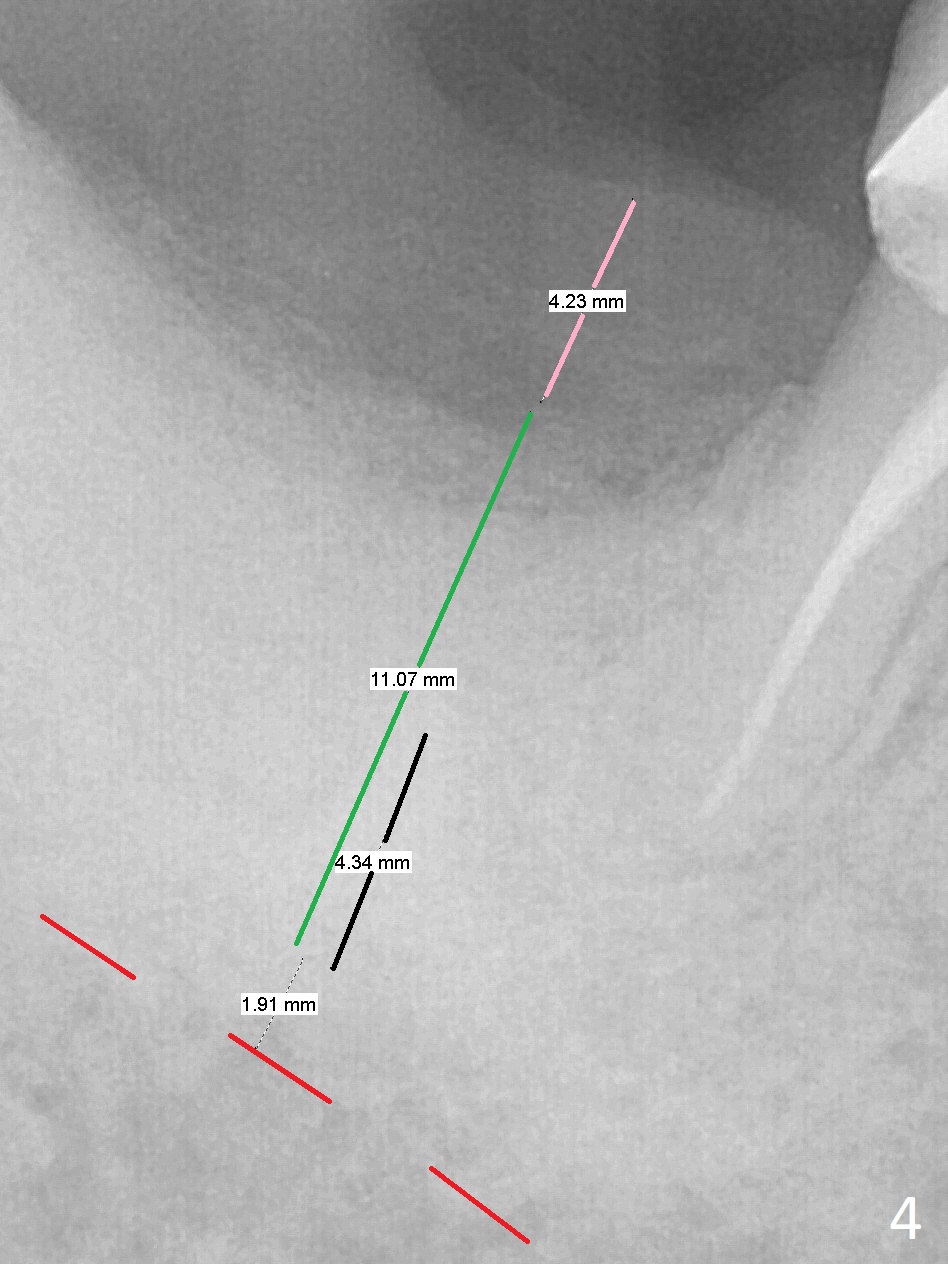

There is a mesiobuccal fistula at #31 with periimplantitis (Fig.1 ^). The bone loss is severe before and after implant removal (Fig.2). It is impossible to place bone-level implant in the original osteotomy due to insufficient bone height. There is pain when a new osteotomy is being initiated in the mesial slope. Following placement of Vera Graft (Fig.3), collagen plug and 6-month resorbable membrane, the wound is closed with suture (mild tension). Postop, there is oozing. Periodontal dressing should have been applied. If the ridge can be preserved in 4-6 months, a 11 mm long implant (Fig.4 green line with 4 mm of the native bone) can be placed with 1.9 mm clearance (red dashed line: the superior border of the Inferior Alveolar Canal); the abutment is estimated to have 4 mm cuff (pink). The socket appears to be healing 8 days postop (Fig.5). The ridge remains wide 5 months post implant removal, although the bone density is low (Fig.6,7 (still ~ 1000 units). It seems that a 5x11.5 mm implant could be placed in the mesiobuccal aspect of the bony defect (Fig.8). For better occlusion, the implant should be shorter (5x8.5 mm) after discussion with the guide lab (Fig.9). Make sure that the most coronal thread is buried by the bone graft, i.e., underneath the crest(>).